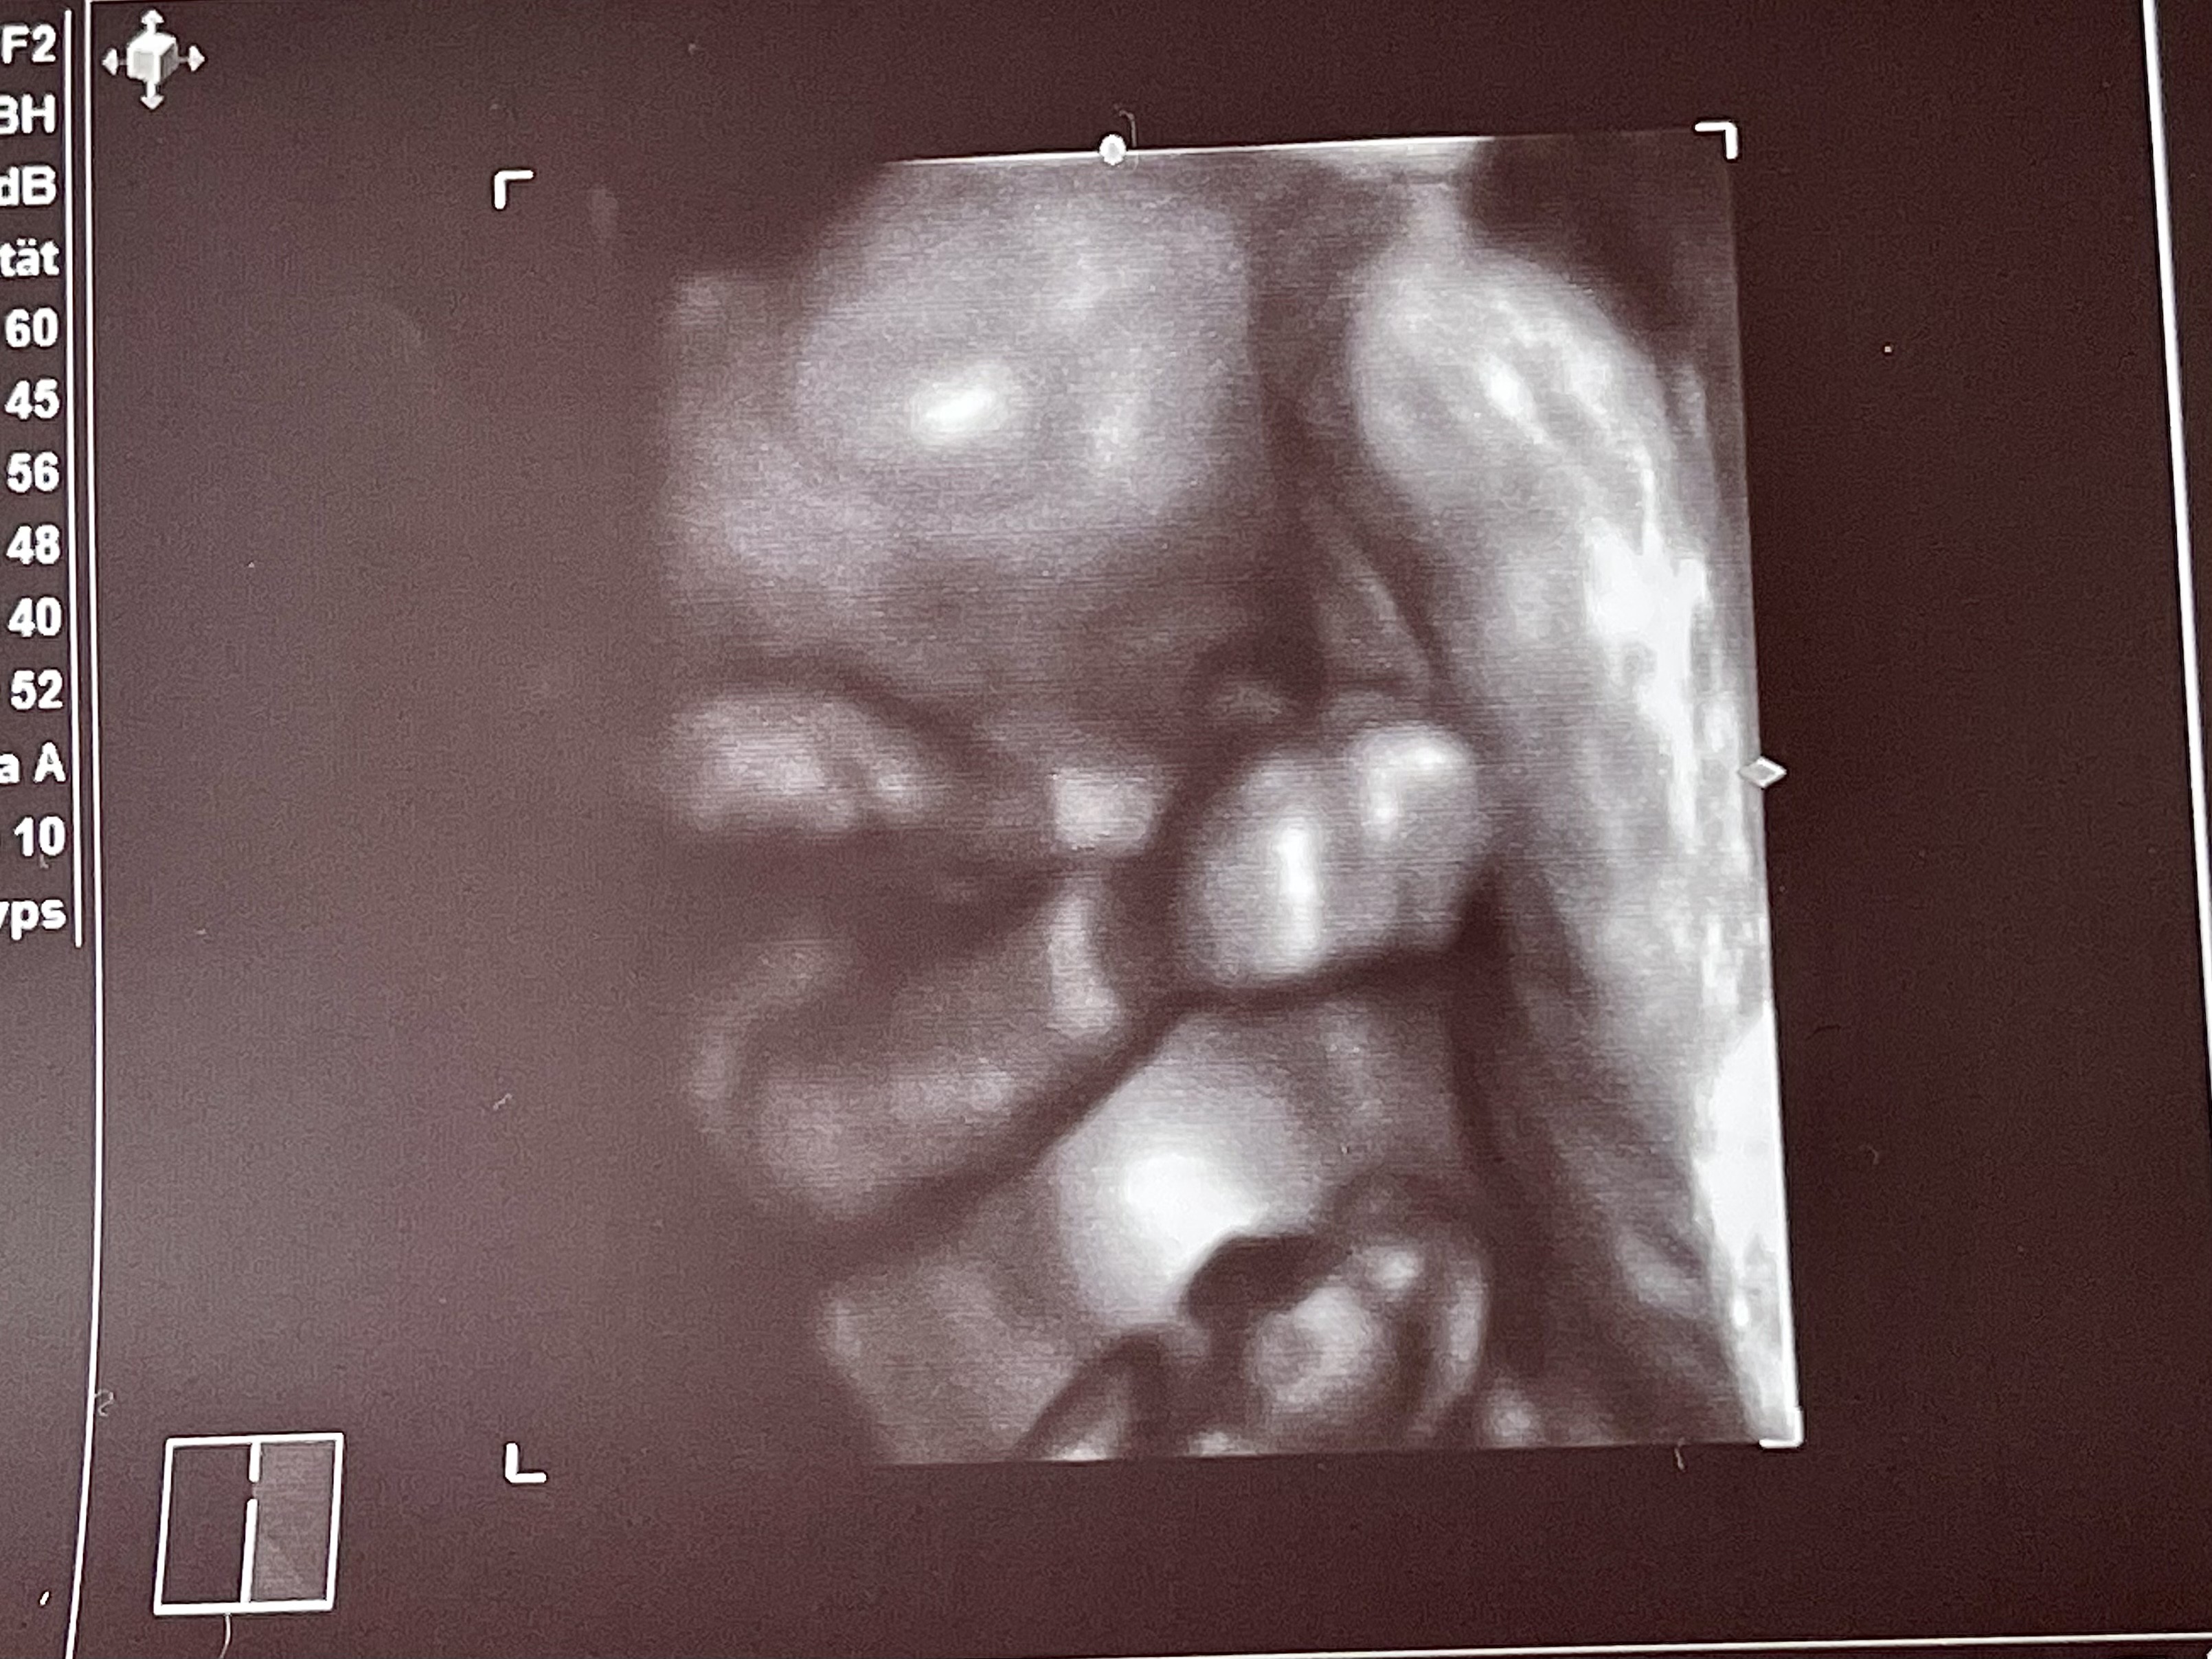

Dzisiaj miałam wizytę (21+5). Młody był bardzo ruchliwy i zasłaniał się rączkami [emoji2370][emoji28]. Wszystko jest dobrze, także bardzo się cieszę.

Zobacz załącznik 1291666